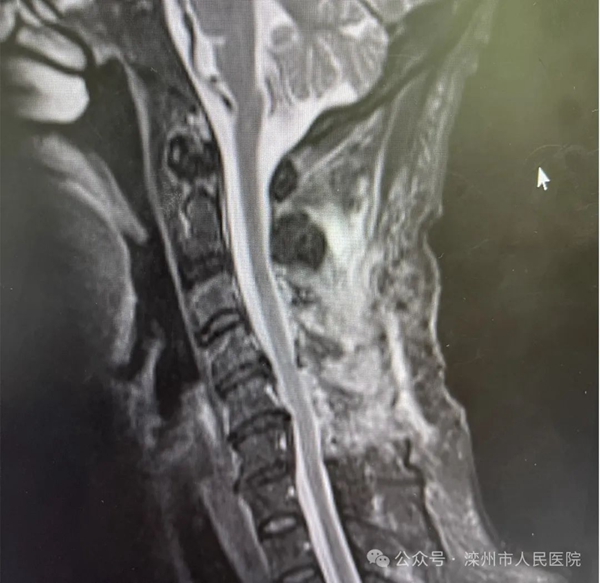

“頸”益求精,與時間賽跑近日,灤州市人民醫(yī)院脊柱及骨病科成功完成一例極其罕見的頸椎管內(nèi)硬膜外血腫清除手術。術后兩天,患者...